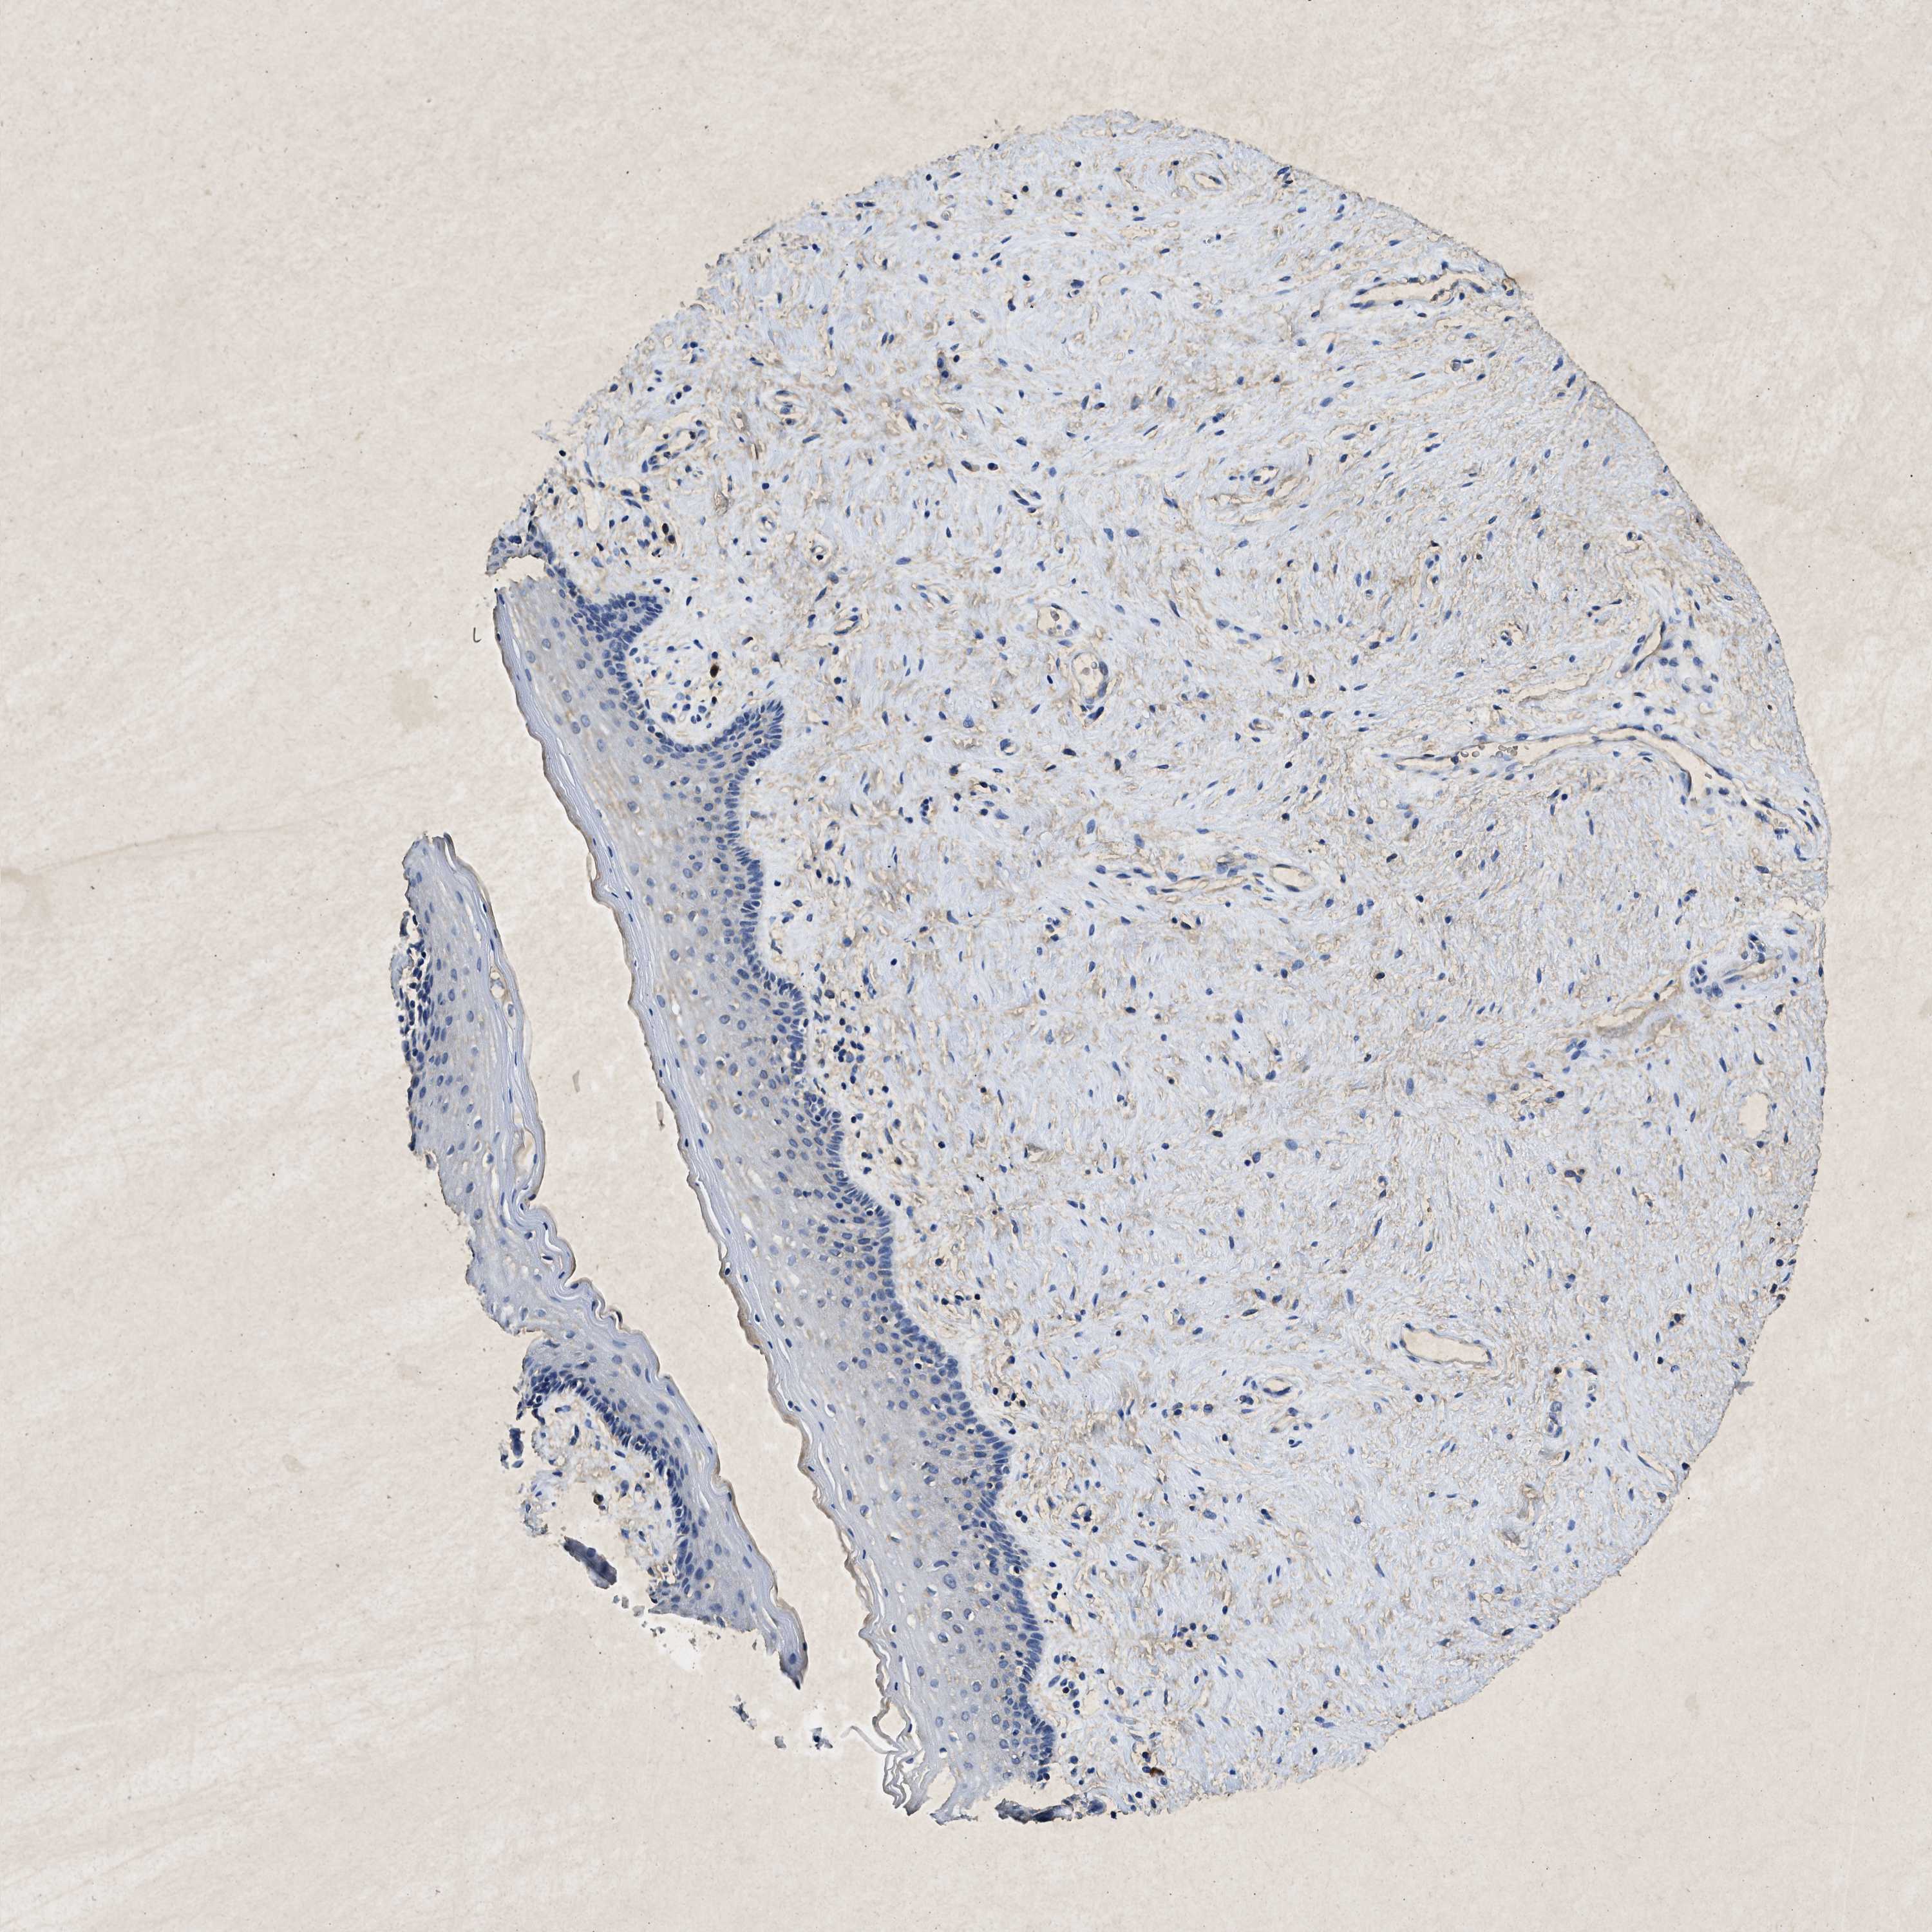

KCNQ1